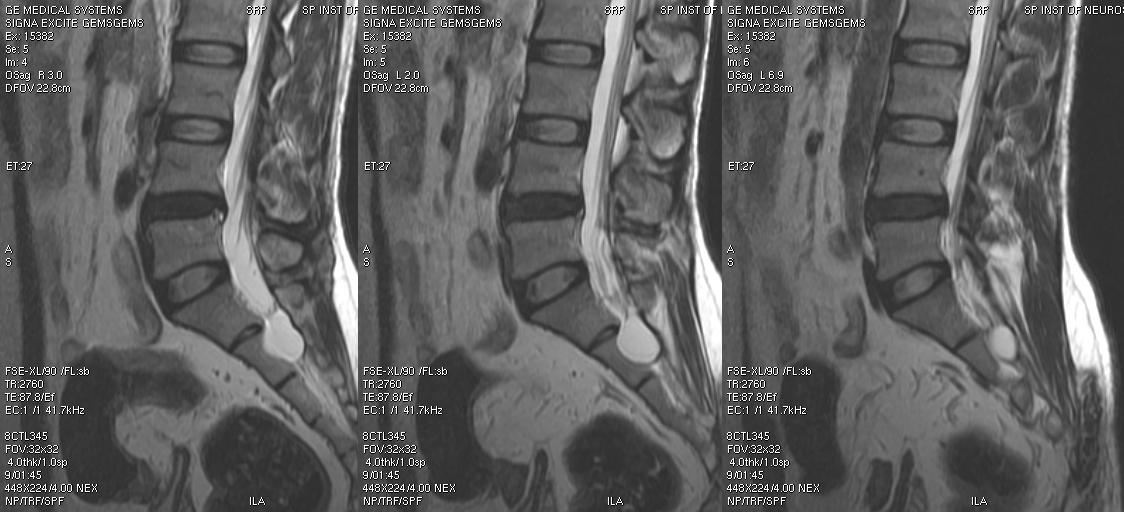

Лечение кистозной опухоли происходит только после постановки точного диагноза, полученного на основе тщательного осмотра пациента, исследования общего и биохимического анализов крови, компьютерной томографии (КТ), миелографии, магнитно-резонансной томографии (МРТ).

Для диагностики кисты позвоночника необходимо провести ряд исследований. Пациенту обязательно назначают магнитно-резонансную и компьютерную томографию, биопсию, ультразвуковое исследование.

Методы диагностики

Наличие кисты позвоночника диагностирует нейрохирург. Специалист назначает комплексное обследование, которое включает:

- Сбор информации о перенесенных пациентом заболеваниях.

- Первичный осмотр пациента, выслушивание жалоб.

- Рентгеноскопию позвоночника (с нескольких сторон).

- МРТ головного и спинного мозга.

- УЗИ позвоночника и поясницы.

- Миелографию. В спинномозговой канал вводят контрастную жидкость, что позволяет обнаружить нарушения в проводящих путях.

- Электромиографию. Процедура позволяет проводить исследования спинномозговых корешков.

Чтобы назначить соответствующее лечение, на этапе диагностики уточняется стадия развития и тип кисты.

Диагностические мероприятия

Обследованием и лечением кисты позвоночника занимается врач-нейрохирург. Специалист проводит осмотр и назначает лабораторные тесты, чтобы поставить точный диагноз.

Для диагностики заболевания используются следующие методы:

- осмотр, пальпация позвоночника;

- рентген в нескольких проекциях;

- магнитно-резонансная томография (МРТ);

- компьютерная томография (КТ);

- ультразвуковое исследование позвоночника (УЗИ);

- миелография;

- электромиография помогает проанализировать состояние спинномозговых корешков;

- анализ крови, мочи, биохимические исследования.

Врач учитывает жалобы пациента, старается определить причину возникновения патологических процессов, оценивает степень тяжести заболевания, выраженность и локализацию сопровождающих признаков — расстройства чувствительности и двигательной активности.

Миелография представляет собой метод диагностики с использованием контрастного вещества. Его вводят в канал спинного мозга, делают рентген и смотрят по результатам проходимость, нарушенную опухолью.